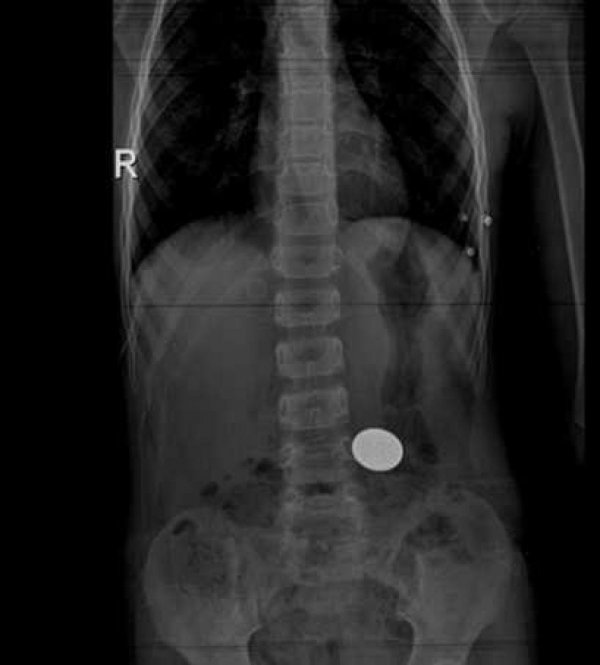

5 yaşındaki çocuğun yuttuğu madeni para endoskopiyle çıkarıldı

Denizli'de 5 yaşındaki çocuğun yuttuğu madeni para, endoskopiyle midesinden çıkarıldı.

Pamukkale Üniversitesinden (PAÜ) yapılan yazılı açıklamada, Çocuk Sağlığı ve Hastalıkları Anabilim Dalına gelen ve 50 kuruş yuttuğu belirtilen 5 yaşındaki Tayfun Demir'in, endoskopik müdahaleyle sağlığına kavuştuğu belirtildi.

"Yutulan yabancı cismin kesici, delici olup olmamasına, boyutuna ve özelliğine göre çocuğu değerlendirip yabancı cismin kendiliğinden sindirim kanalını terk etmesini bekleme ya da yabancı cismin bulunduğu yere göre ağızdan ya da makattan endoskopi aracılığıyla çıkarılma işlemi yolunu seçiyoruz. Son olarak bize başvuran minik hastamızın da midesindeki madeni parayı endoskopik olarak ağzından başarıyla çıkardık. Midede bulunan madeni para kesici ve delici olmadığı için nispeten düşük bir risk oluştursa da hastamıza endoskopik müdahale yaparak oluşabilecek problemleri önlemiş olduk."